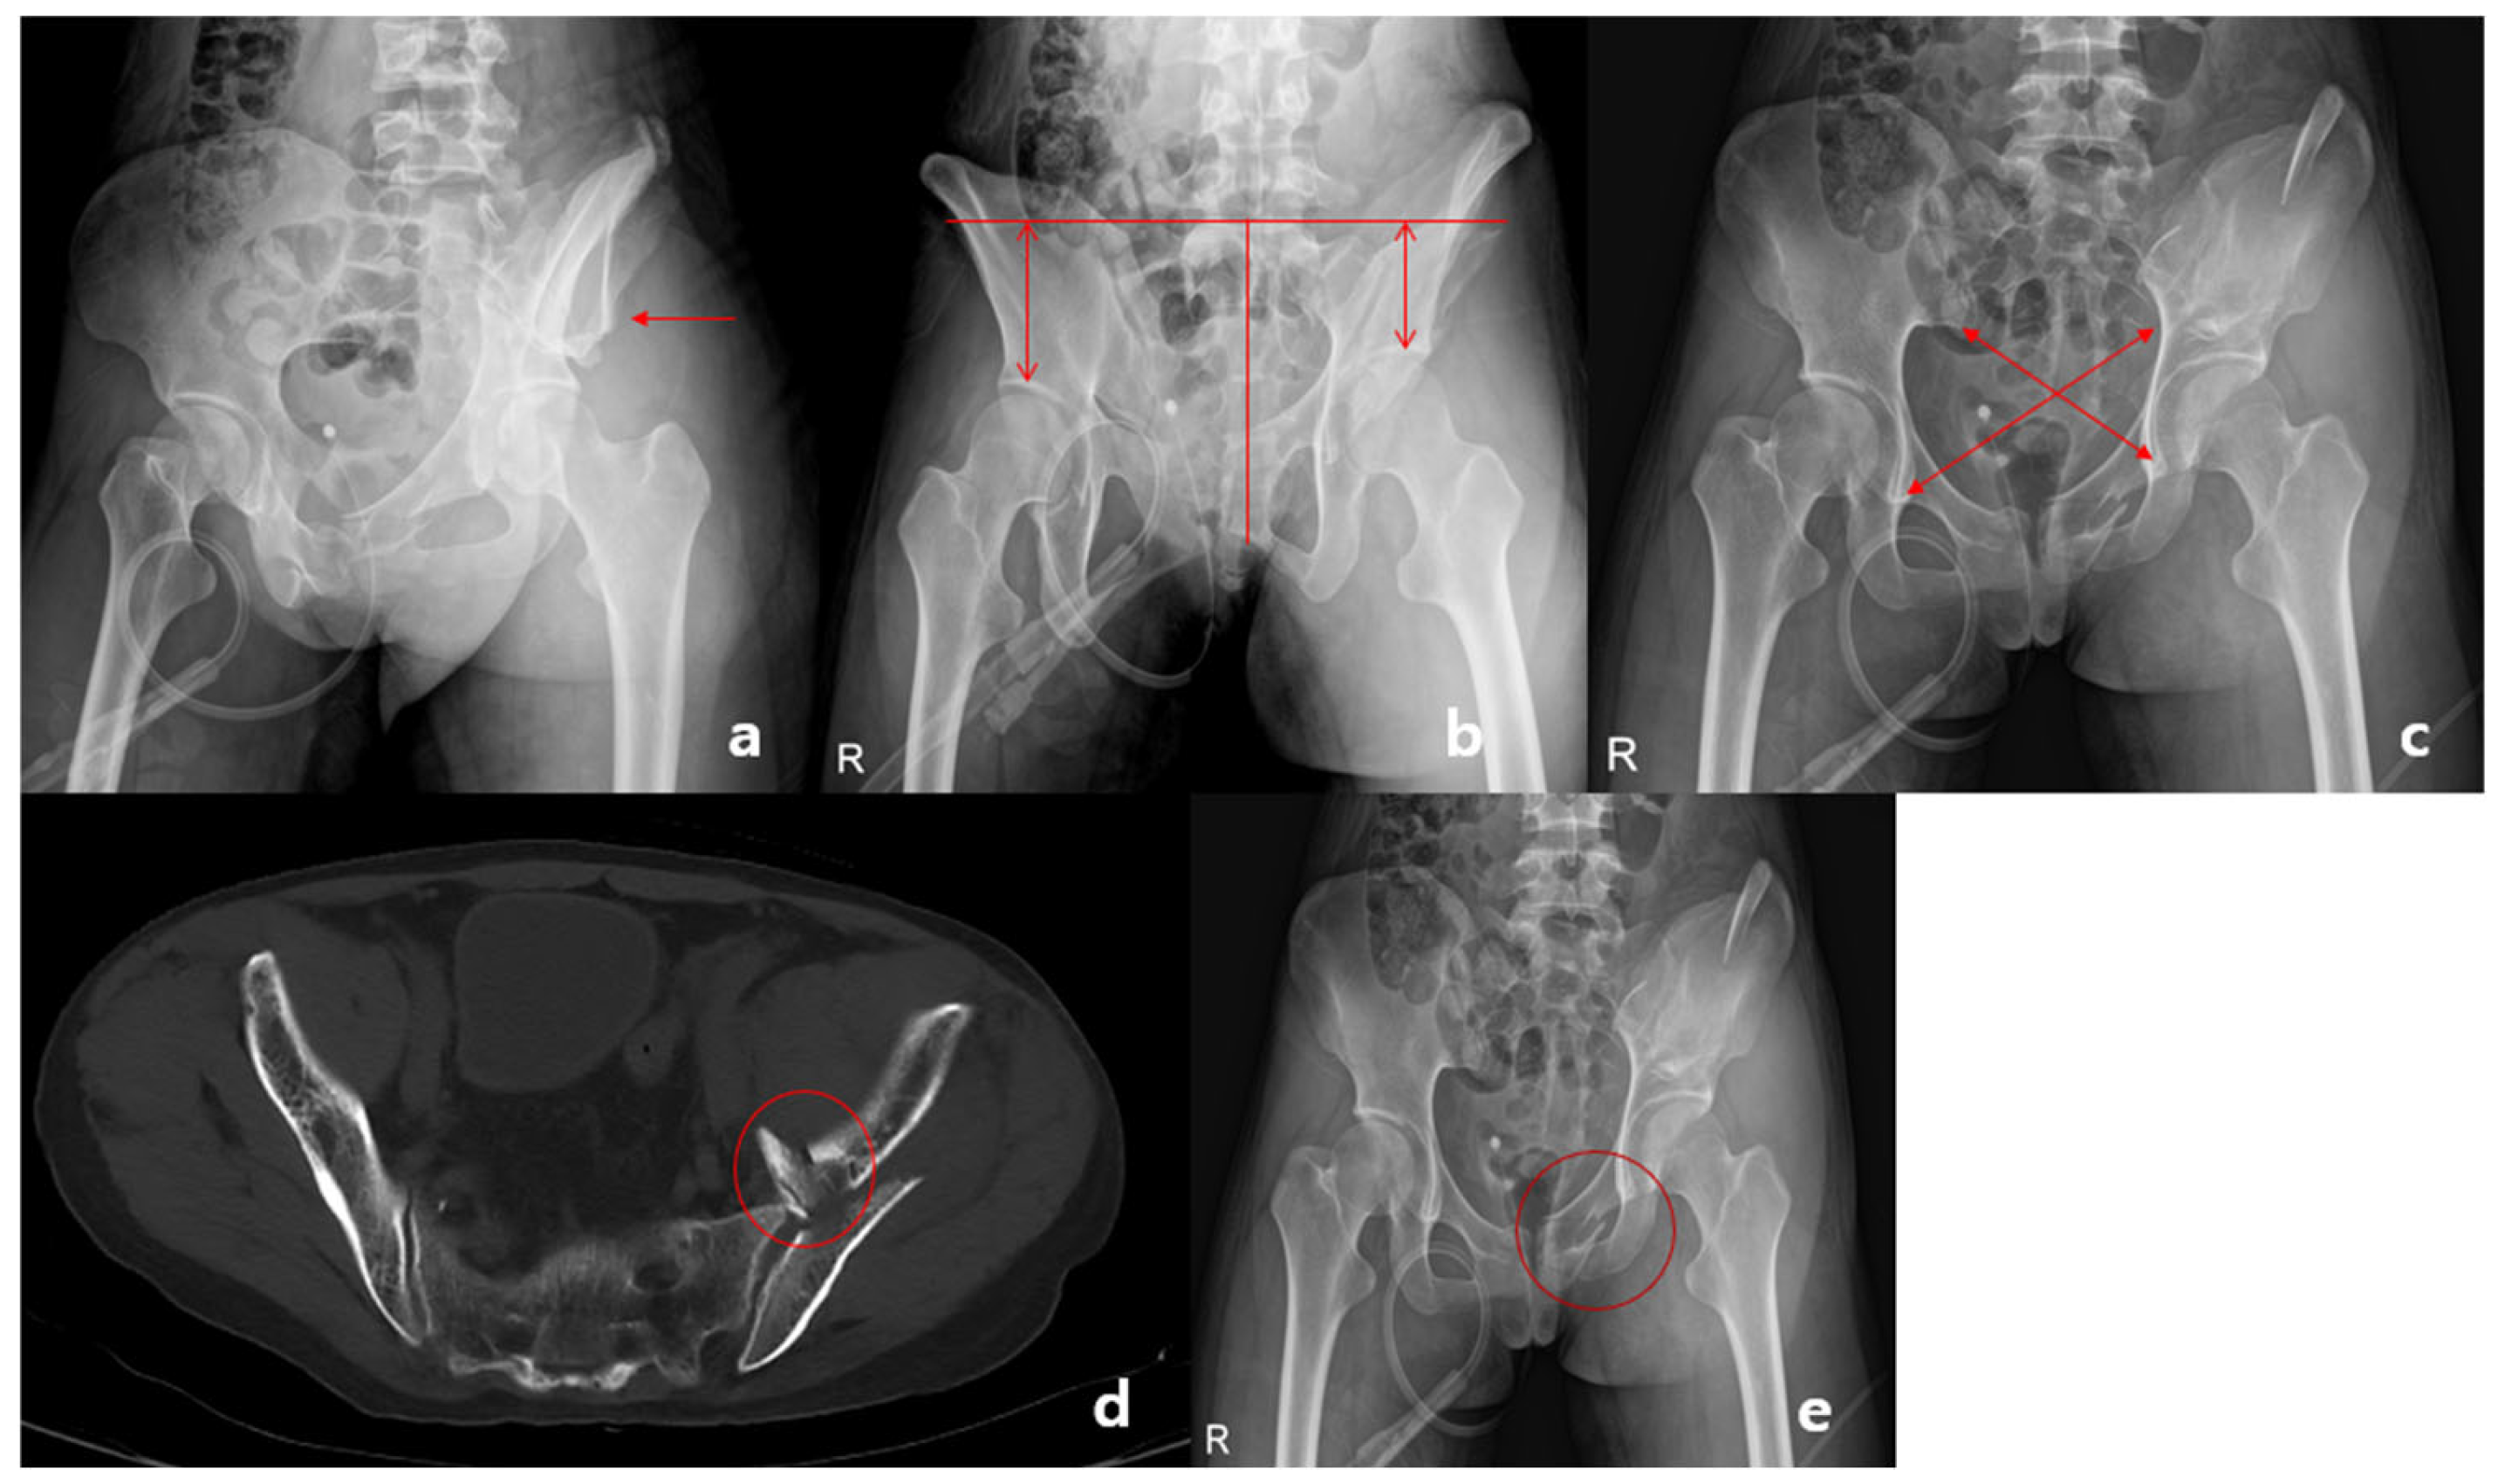

2.3. Radiologic Assessment

2.4. Assessment of Vertical Displacement

2.5. Assessment of Rotational Displacement